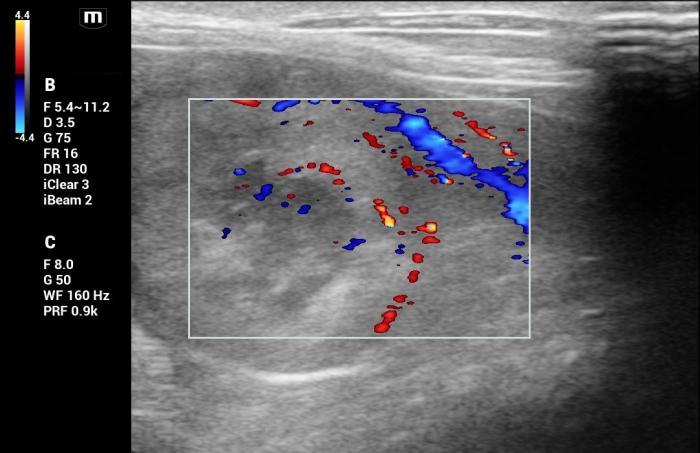

La lesión deformaba la morfología de la cola esplénica y mostraba señal Doppler color positiva, principalmente periférica (Figura25).

Hallazgos elastográficos (Natural Touch Elastography®): el nódulo presentó una rigidez marcadamente aumentada respecto del parénquima esplénico circundante, con patrón elastográfico heterogéneo (“dureza mixta”), caracterizado por áreas internas de elevada velocidad de onda de corte (Figura 26-27).

Este comportamiento se alinea con los hallazgos reportados para lesiones malignas esplénicas, que tienden a presentar valores superiores a 3 m/s según la evidencia publicada5.